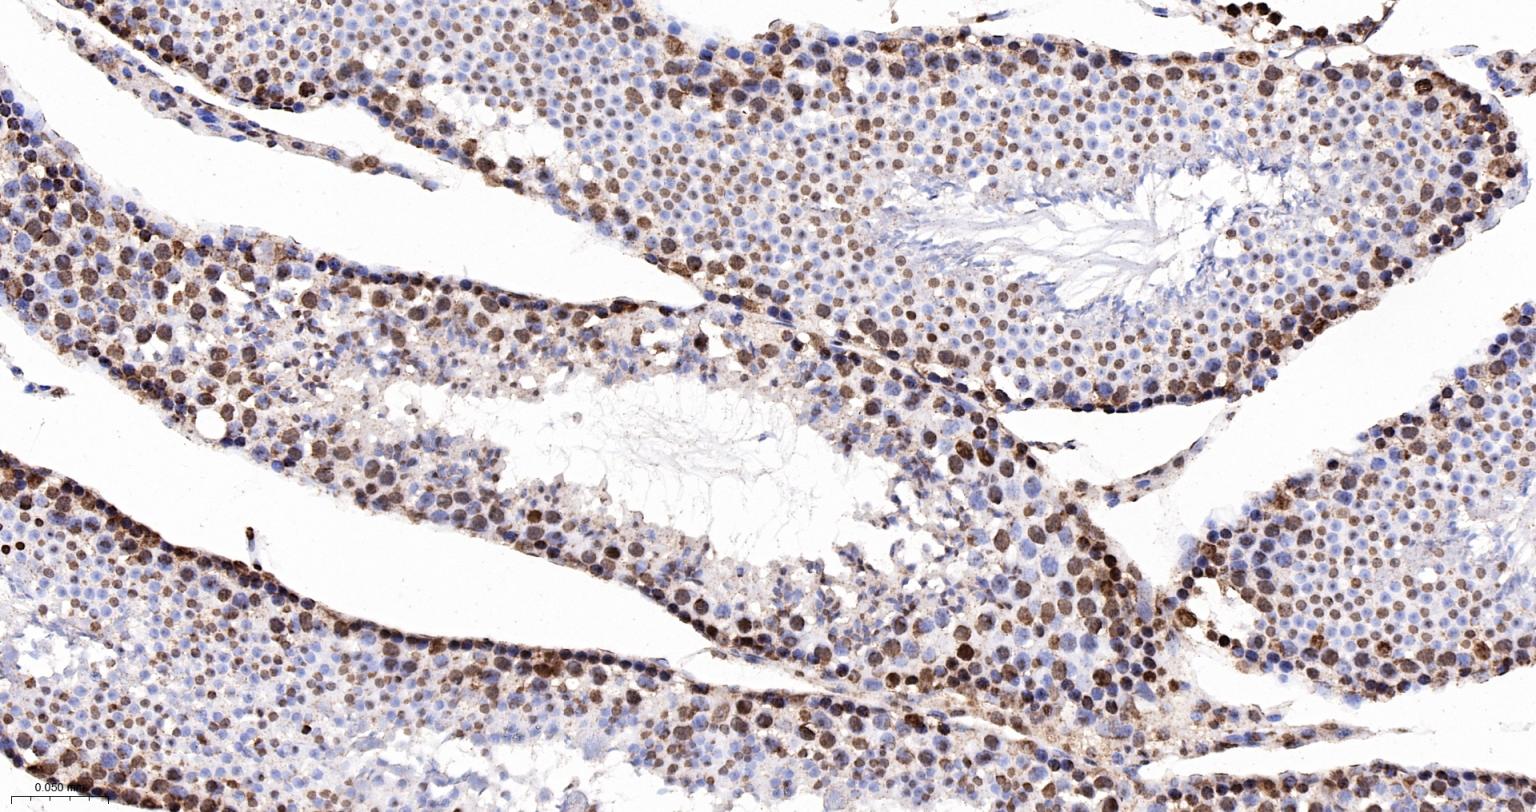

Paraformaldehyde-fixed, paraffin embedded Human Breast Cancer; Antigen retrieval by boiling in sodium citrate buffer (pH6.0) for 15 min; The section was incubated with hnRNP K Monoclonal Antibody, Unconjugated (bsm-61246R) at 1:200 overnight at 4°C, followed by conjugation to the bs-0295G-HRP and DAB (C-0010) staining.